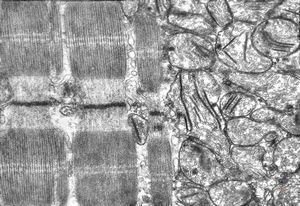

rat | skeletal muscle 6h. post ex. … changes of mitochondrial cristae